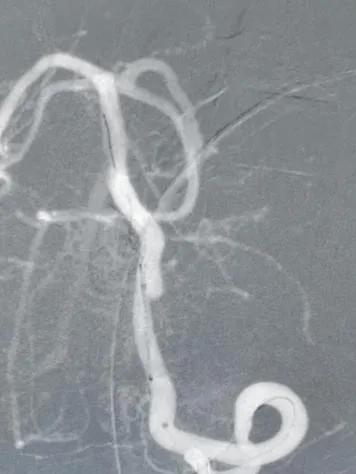

术后图像

造影显示病变部位造影剂滞留。载瘤动脉通畅,脊髓前动脉通畅。后分别行左右颈内动脉及右侧椎动脉正侧位造影,未见明显血管异常。

结束手术,患者麻醉清醒后安全返回病房,无神经功能缺失。7天后,患者康复出院。限期随访。